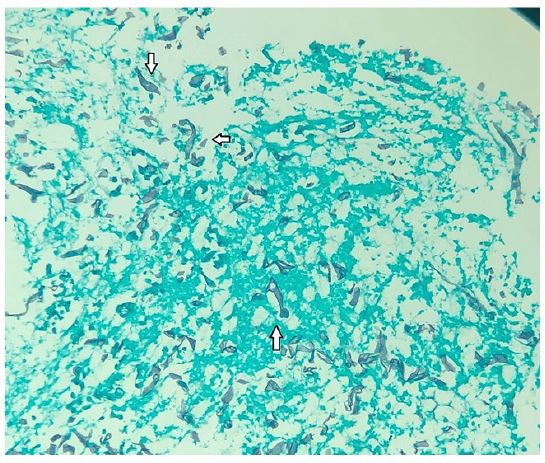

During his stay in the intensive care unit, he was treated with ceftriaxone and azithromycin, however his white blood cell count increased (Table 1), and clinical condition worsened, requiring an escalation of the antimicrobial spectrum to piperacillin and tazobactam (4,5 g qid) over the following two weeks, and later meropenem (1G tid) associated with teicoplanin (400 mg sid). In addition, the patient developed oliguria and renal dysfunction secondary to septic shock, requiring renal replacement therapy with hemodialysis. After 2 weeks in ICU, the patient developed upper gastrointestinal bleeding, with melena and a drop in hemoglobin. An upper digestive endoscopy was requested, which showed an ulceroinfiltrative lesion in the fundus and gastric body, measuring approximately 70 mm, and no signs of active bleeding and no need for endoscopic therapy (Figure 1). Biopsies of the lesion were performed, which demonstrated active, chronic ulcerated inflammation, with numerous short and irregular segments of hyphae amidst necrotic debris, without cellular atypicality, findings suggestive of mucormycosis (Figure 2).

Figure 2: Histology with Grocott-Gomori silver methenamine staining, demonstrating short and irregular segments of hyphae, amidst necrotic debris, Suggestive with Zygomycetes. Short and irregular segments of hyphae (arrows).